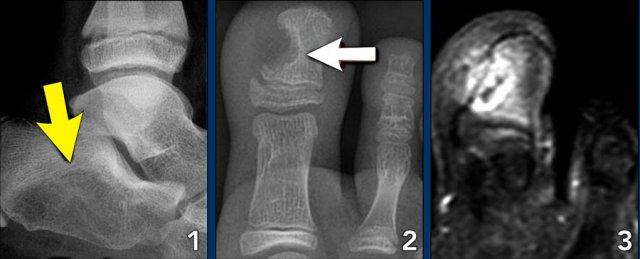

Foot lesions

Here some typical examples of bone tumors in the foot:

- Ewing sarcoma in the calcaneus

- Glomus tumor

- Same patient MRI